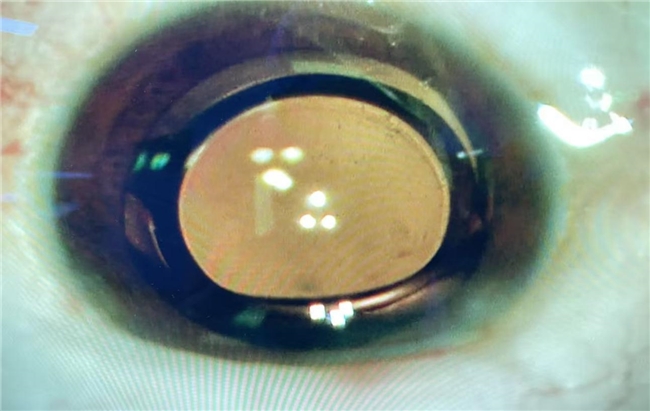

作为TECNIS平台上的新一代功能型人工晶状体,强生眼力健臻无级®凭借其创新的纯折射设计理念和高水平的工业制造水准,致力于为白内障患者,尤其是追求高品质视觉的屈光性白内障患者,提供更接近自然眼的视觉体验。它不仅能实现平滑连续的视力范围,更显著降低了恼人的光学干扰,如眩光、光晕。同时,其更宽广的有效光学区设计,提升了视力稳定性,即使在术后存在微小屈光误差的情况下,也能保持良好的视觉清晰度,让患者无论是白天工作生活、夜间出行驾驶,还是使用电子产品,都能获得舒适、稳定、自然的高质量视力。

谈及此次手术,吴教授表示:“在临床中,我们发现大部分的白内障患者都存在屈光不正的问题,他们除了希望术后能够摆脱白内障之外,也希望能够实现摘镜自由,能够像年轻时一样,自由切换远、中、近距离的清晰视觉。而臻无级®这款人工晶状体的设计理念,正是回归人眼自然晶状体的光学规律。本次手术的患者是一位10年前做过初代全飞秒屈光手术的患者,患者目前从事企业管理方面的工作,对全程视力要求高,且乐于接受新事物,经过对患者的眼睛进行详细的检查和评估,并与患者充分沟通其用眼需求后,我们建议选择了臻无级®这款人工晶体。臻无级®采用的纯折射技术在光学干扰上可控制在近似单焦点的水平,很大程度上减少了患者术后存在的眩光、光晕等问题,对于这类做过屈光手术的患者来说术后视觉质量改善更明显,且包容性更好,同时也能实现从看远到看近的连续视力。术后第一天患者远中近视力就达到了:1.0,1.0,0.8,视力得到明显的改善提升,患者非常满意!“